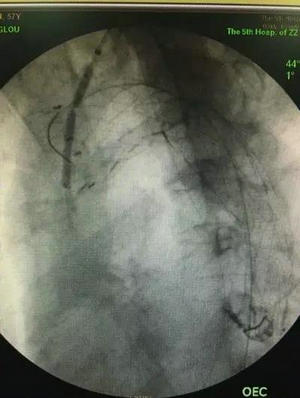

激光开窗并球囊扩张

王兵教授带领血管外科团队为患者量身打造了一套切实可行的个体化治疗手术方案,即应用目前最先进的“激光原位开窗联合胸主动脉腔内修复术”进行治疗。也就是应用多尼尔半导体激光光纤产生点状高温灼烧主动脉覆膜支架,使其产生点状灼烧孔,从孔中植入支撑导丝,球囊扩张使该孔径增大,从孔中置入支架,使弓上动脉与覆膜支架腔内沟通,保存血流及上肢或颅脑血供。